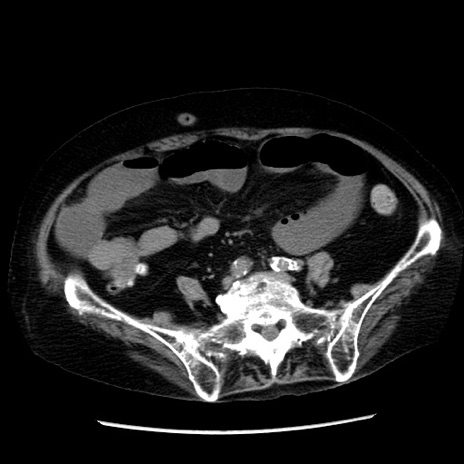

症例14(横断像)

【症例】 90歳代女性

【主訴】 腹痛・嘔吐

【現病歴】今朝から左側腹部痛を認めた。 経過観察していたが、嘔吐を認めたため来院。

【既往歴】 子宮癌術後

【身体所見】 意識清明、BP 127/54mmHg、P 98bpm Sp02 95%(RA)、BT 35.8°C、腹部平坦・軟腸ぜん動音聴取良好、右下腹部圧痛(+) 反跳痛なし

【データ】WBC 9800、CRP 0.46